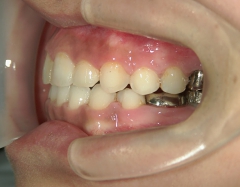

矯正歯科 治療前 上顎を装置(QH)で拡大後ワイヤー矯正へ移行、右下5番左下4番 計2本抜歯叢生改善

no.28_6958_治療前_右.jpgno.28_6958_治療前_正面.jpgno.28_6958_治療前_左.jpg